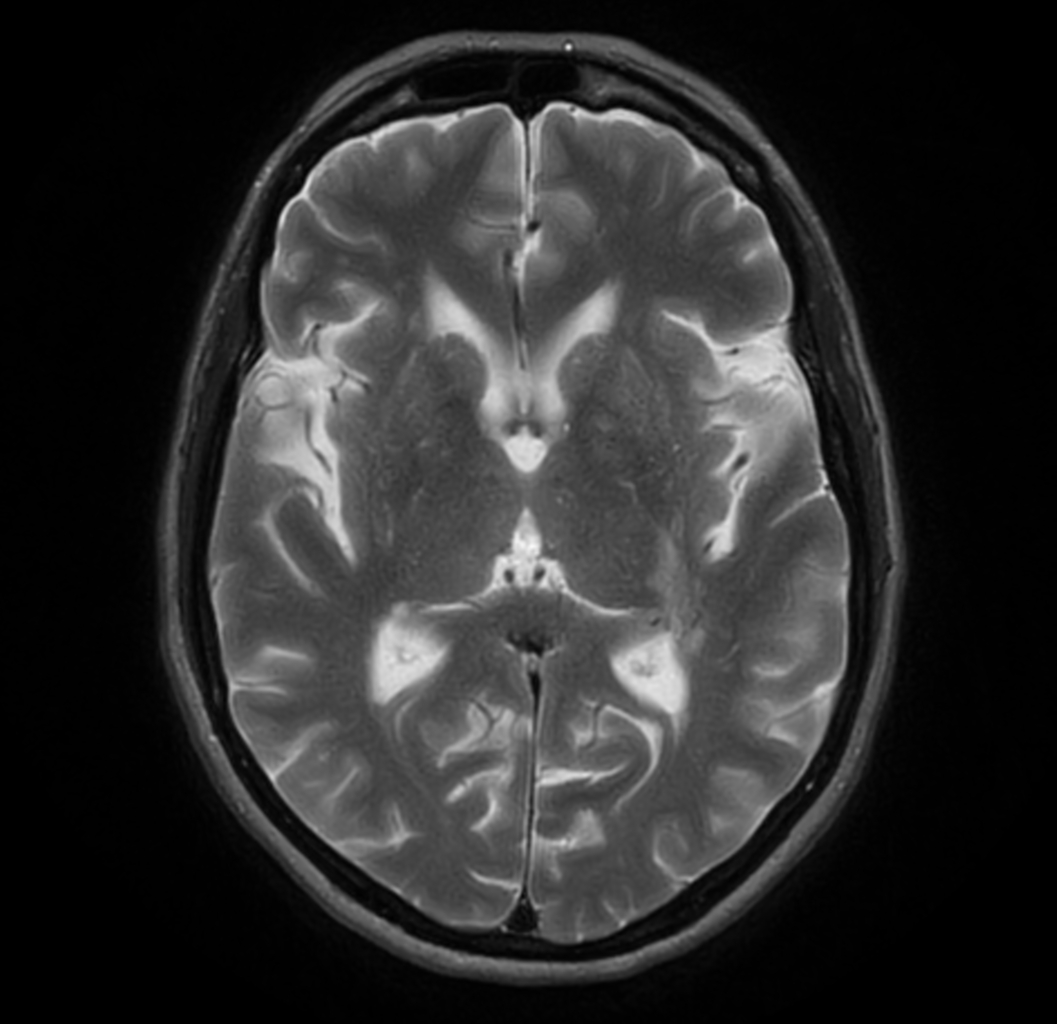

3D VIEW - T2w FLAIR (axial reformat)

-